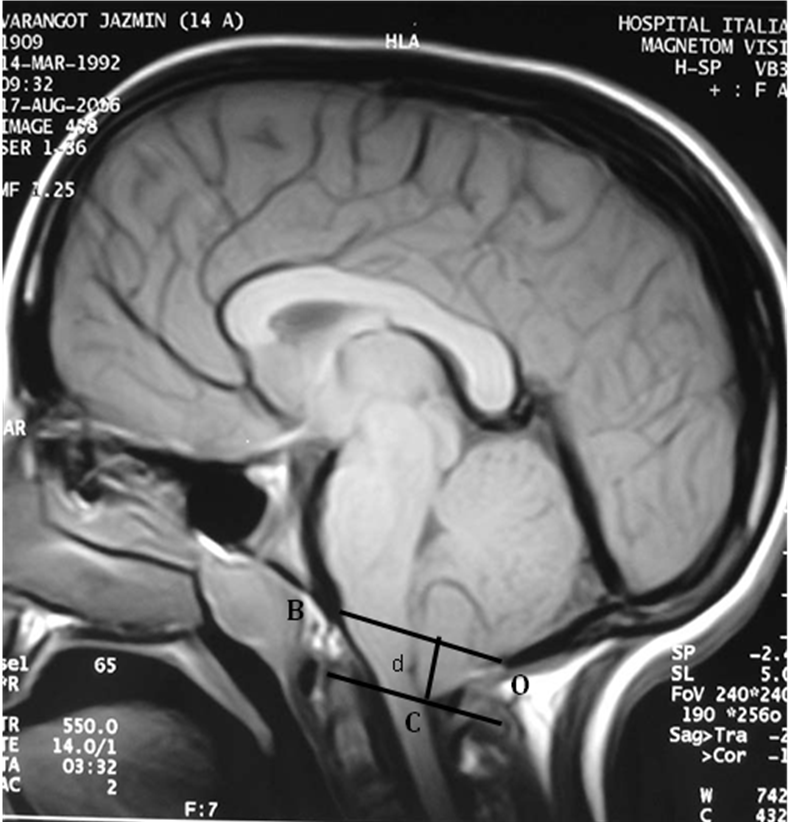

Análisis con resonancia magnética de la posición de la amígdala cerebelosa antes de la corrección instrumentada por vía posterior y después de ella en pacientes con escoliosis idiopática del adolescente. [Magnetic resonance imaging evaluation of the position of the cerebellar tonsil before and after posterior spinal fusion in adolescent idiopathic scoliosis].

3. Aboulezz AO, Sartor K, Geyer CA, et al. Position of cerebellar tonsils in normal population and in patients with Chiari malformation: a quantitative approach with MR imaging. J Comput Assist Tomogr 1985;9:1033–6.

4. Barkovich AJ, Wippold FJ, Sherman JL, et al. Significance of cerebellar tonsilar position on MR. AJNR Am J Neuroradiol 1986;7:795–9.

13. Cheng JC, Chau WW, Guo X, et al. Redefining the magnetic resonance imaging reference level for the cerebellar tonsil: a study of 170 adolescents with normal versus idiopathic scoliosis. Spine 2003;28:815–8.

14. Sun X, Qiu Y, Zhu Z, Zhu F, et al. Variation of the position of the cerebellar tonsil in idiopathic scoliosis with Cobb angle > 40º. A magnetic resonance imaging study. Spine 2007;32(15):1680-1686.